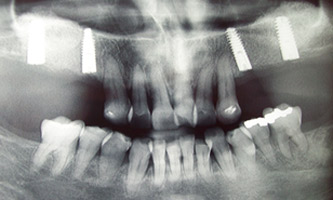

Kirurgija / implantologija

Dentalni laboratorij